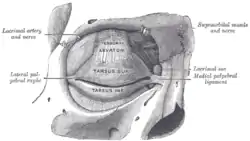

The tarsi and their ligaments. Right eye; front view. | |

The tarsi (SG: tarsus) or tarsal plates are two comparatively thick, elongated plates of dense connective tissue, about 10 mm (0.39 in) in length for the upper eyelid and 5 mm for the lower eyelid; one is found in each eyelid, and contributes to its form and support. They are located directly above the lid margins.[1] The tarsus has a lower and upper part making up the palpebrae.

Superior

The superior tarsus (tarsus superior; superior tarsal plate), the larger, is of a semilunar form, about 10 mm (0.4 in) in breadth at the center, and gradually narrowing toward its extremities. It is adjoined by the superior tarsal muscle.

To the anterior surface of this plate the aponeurosis of the levator palpebrae superioris is attached.

Inferior

The inferior tarsus (tarsus inferior; inferior tarsal plate) is smaller, is thin, is elliptical in form, and has a vertical diameter of about 5 mm (0.2 in). The free or ciliary margins of these plates are thick and straight.

Relations

The attached or orbital margins are connected to the circumference of the orbit by the orbital septum.

The lateral angles are attached to the zygomatic bone by the lateral palpebral raphe.

The medial angles of the two plates end at the lacrimal lake, and are attached to the frontal process of the maxilla by the medial palpebral ligament).

The sulcus subtarsalis is a groove in the inner surface of each eyelid.